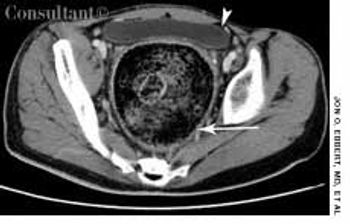

A 14-year-old boy presented with a 3-day history ofrunny nose, cough, and fever. His temperature was37.7°C (100ºF); heart rate, 78 beats per minute; and respirationrate, 26 breaths per minute. Several symmetric,circular ecchymotic lesions that measured 4 cm in diameterwere noted on the upper chest. There was no evidenceof external injury to other parts of the body. Thechild reported that the bruises resulted from cupping,performed by a Chinese practitioner in an attempt torelieve the fever.